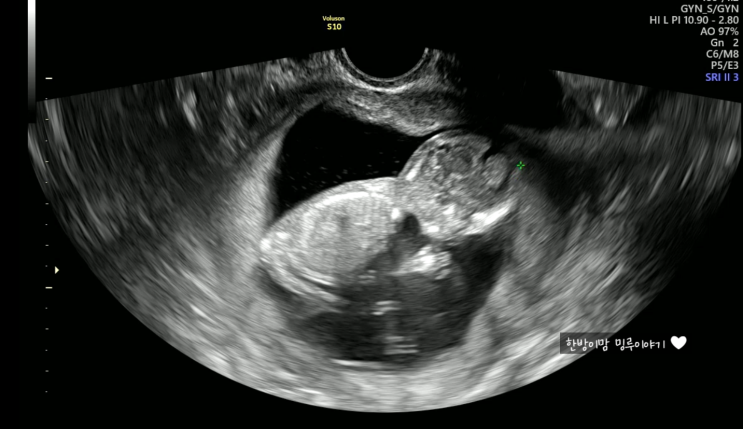

임신중일기_6. 30주차 초음파. 얼굴 보기 힘든 한방이, 손은 야무지게 생겼구나??(한나산부인과 백일해주사, 바우처결제)

이번엔 한나산부인과, 30주 정기검진 이야기!! 예약하고 방문하니, 남편 백일해주사맞는 것까지 30분정도밖...